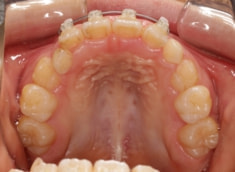

治療開始時